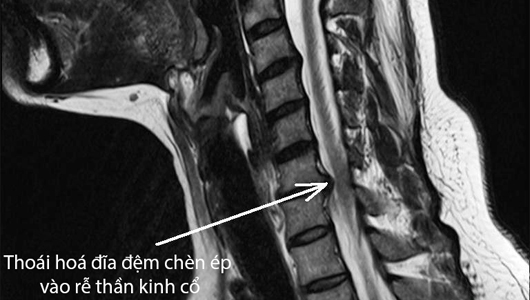

Chèn ép rễ thần kinh có thể xảy ra khi rễ thần kinh trong cột sống bị kích thích hoặc chèn ép bởi một trong nhiều tình trạng sau đây như thoát vị đĩa đệm cột sống, hẹp ống sống, thoái hóa cột sống, hình thành gai xương hay hiếm gặp là các trường hợp có u bướu nội tủy hay từ bên ngoài gây chèn vào.

Ngoài ra, các phương tiện hình ảnh học cũng có vai trò trong chẩn đoán Chèn ép rễ thần kinh. Một phim X-quang thẳng để đánh giá tư thế, cấu trúc của cột sống và chụp cộng hưởng từ giúp đánh giá cấu trúc tủy sống và rễ thần kinh đi ra là các xét nghiệm hình ảnh điển hình được sử dụng để khảo sát bệnh lý tại cột sống nói chung, chẩn đoán Chèn ép rễ thần kinh nói riêng. Tuy nhiên, nếu người bệnh có các chống chỉ định của việc chụp cộng hưởng từ thì chụp cắt lớp vi tính sẽ được chỉ định thay thế.